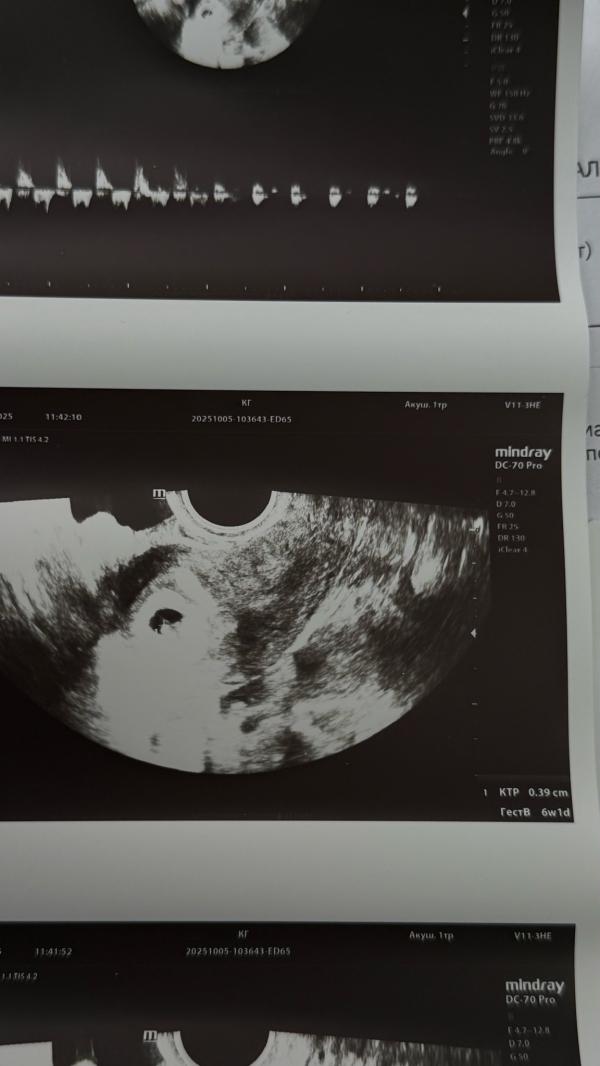

Ты-самое лучшее событие этого года🐣❤️‍🩹